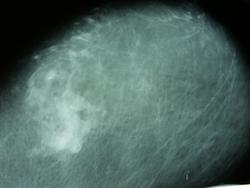

Пол пациента: Женский пол Тип патологии: Другое Область исследования: Другое Методы исследования: Rg Смущает верхний квадрант левой молочной железы ID:36978 Пт, 11/04/2014 - 04:06 #1 vadim losevichev Не на сайте Был на сайте: 7 лет 1 месяц назад Зарегистрирован: 27.01.2013 - 09:45 Публикации: 679 Нужно сравнить с правой плюс снимки в прямых проекциях плюс прицельный. Non progrĕdi est regrĕdi. Пт, 11/04/2014 - 11:35 #2 zolotomoe Не на сайте Был на сайте: 8 лет 12 месяцев назад Зарегистрирован: 10.10.2013 - 11:22 Публикации: 63 Только такой.на других не выводится.учимся-поставили фиброзную мастопатию. Пт, 11/04/2014 - 11:56 #3 Helios Не на сайте Был на сайте: 7 месяцев 2 недели назад Зарегистрирован: 06.08.2010 - 15:16 Публикации: 4417 "Левая мама"...Мама только правой бывает. Пт, 11/04/2014 - 12:59 #4 vadim losevichev Не на сайте Был на сайте: 7 лет 1 месяц назад Зарегистрирован: 27.01.2013 - 09:45 Публикации: 679 Пропальпировать это место лишним не будет. Non progrĕdi est regrĕdi.

Только такой.на других не выводится.учимся-поставили фиброзную мастопатию.